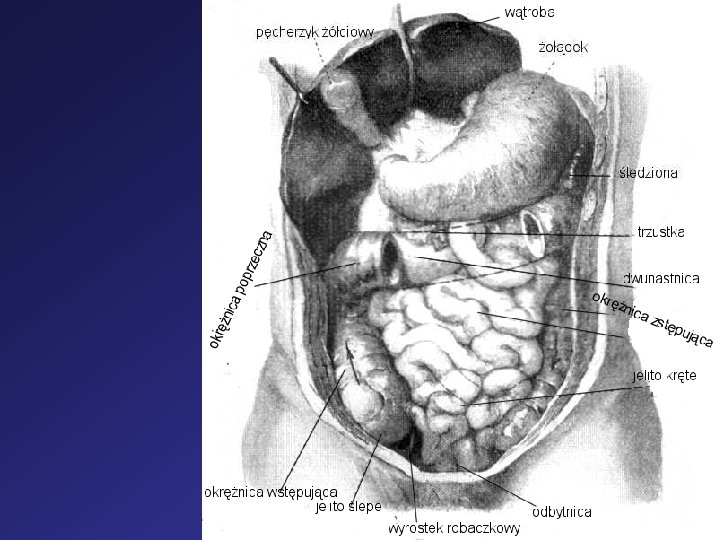

Budowa ciała człowieka: Człowiek zbudowany jest z tułowia, szyi, głowy i czterech kończyn: dwóch kończyn górnych i dwóch kończyn dolnych. Wyróżniamy następujące układy narządów: Układ szkieletowy, w jego skład wchodzą: układ kostny – nauka, która o nim mówi to osteologia układ stawowy – artrologia układ więzadłowy – syndesmologia Układ mięśniowy - miologia Układ pokarmowy – nauka to gastro-enterologia Układ moczowo - płciowy – nauki zajmujące się tymi układami to : układem wydalniczym –nefrologia (nerki), część dolna - urologia układem płciowym żeńskim – ginekologia układem płciowym męskim – andrologia Układ oddechowy – pulmonologia Naukę o układach 3 -5 nazywamy splanchnologią. Układ gruczołów dokrewnych – endokrynologia Układ nerwowy – neurologia Układ narządów zmysłów - estezjologia Skóra- dermatologia